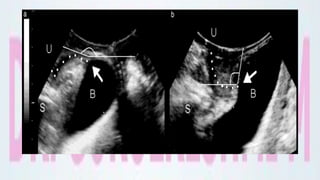

Radiological classification of

cystoceles

Originally proposed by Green,

Based on:

Descent of the bladder neck, retrovesical angle (the angle

between the proximal urethra and the trigonal surface of the

bladder ) and the degree of urethral rotation.

Radiological classification of cystoceles

Green type I is described as cystocele with open retrovesical angle (≥

140°) and urethral rotation < 45°.

Green type II describes a cystocele with open retrovesical angle (≥

140°) and urethral rotation between 45 and 120°, also called

cystourethrocele.

A cystocele with intact retrovesical angle (< 140°) is defined as Green

type III